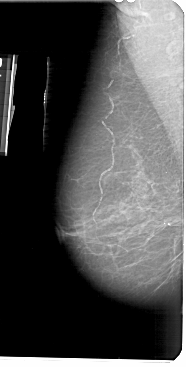

A_1737_1.LEFT_CC

LEFT_CC LINES 5356 PIXELS_PER_LINE 2611 BITS_PER_PIXEL 12 RESOLUTION 43.5 NON_OVERLAY